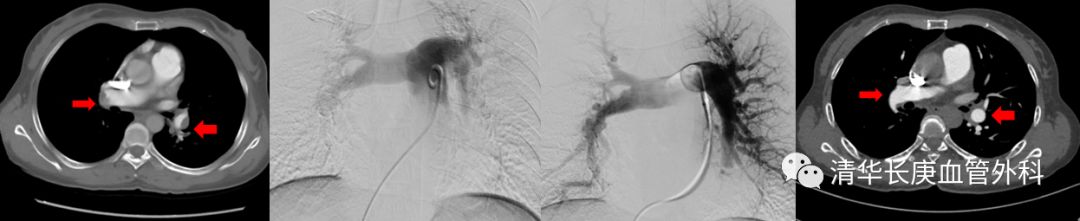

患者张某,女性,49岁,反复发作胸痛、憋气症状3年,1年前再次急性发作,就诊我院血管外科,诊断为肺栓塞、慢性血栓栓塞性肺动脉高压,肺动脉压力高达96mmHg。考虑患者复发肺动脉栓塞可能,经微创肺动脉栓塞腔内溶栓治疗后症状缓解,肺动脉压力降至70mmHg左右。此后患者坚持药物治疗,但仍有活动后喘憋等症状,近1年肺动脉压力逐渐升高至70-80mmHg,间断发作右心衰竭,最严重时6min步行距离只有不足100m,严重影响日常生活,时刻危及患者生命。

(术前双侧肺动脉主干内血栓,术中溶栓后改善,术后复查主干血栓消失)